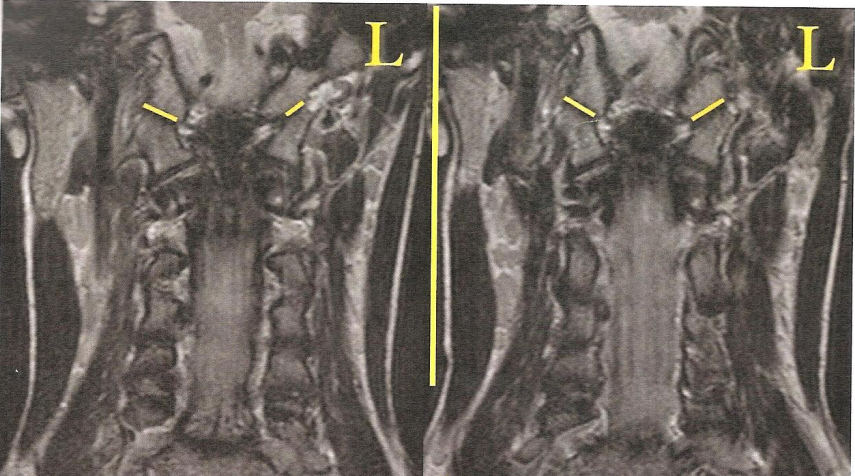

На снимках МРТ стрелками обозначен смещённый первый шейный позвонок (изображение слева); светлые пятна (на изображении справа) обозначают боковые массы атланта; асимметрия говорит о том, что позвонок повёрнут

Снимки МРТ: слева - атлант смещён, справа - нормальное положение атланта после атластерапии